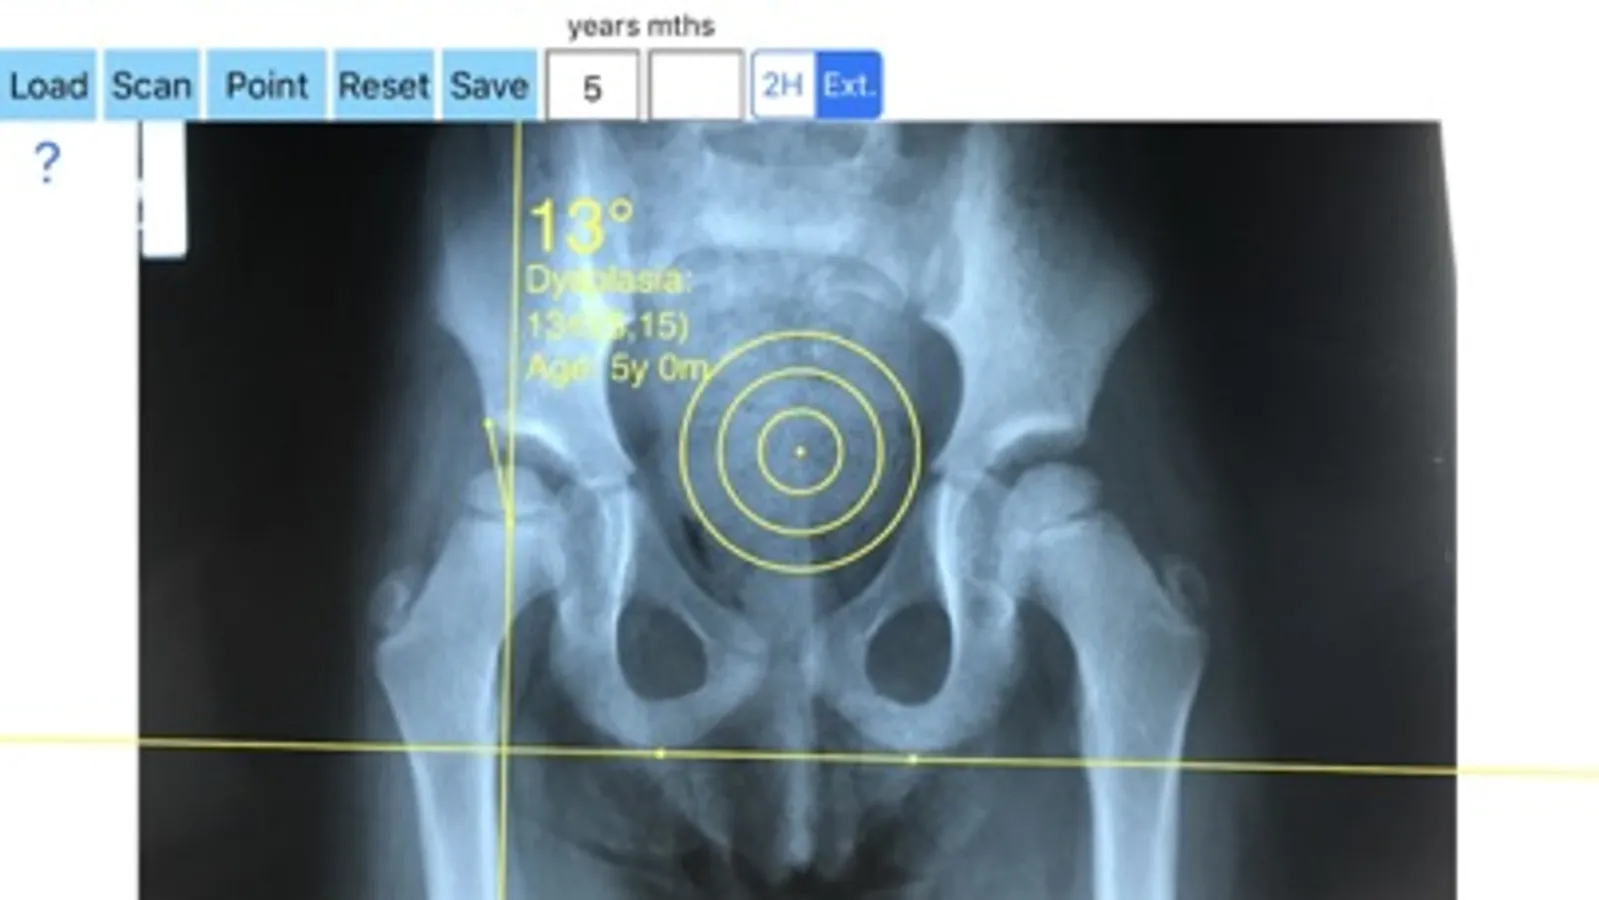

-Securely import medical images directly from the camera or stored photos

-Offers a very convenient way to determine the most accurate possibly lines in order to measure the angles. By the aid of a circular transparent template, the points of interest are marked accurately. The automatically formed lines, drawn between points, measure automatically the angles of interest. The results are printed in degrees. By inputting the age, the measured angle is compared with values from normal reference database. In case the measured angle is beyond the normal range for that age, the hips are categorized as normal, borderline dysplastic, dysplastic or severe dysplastic or over coveraged, pincer type femuracetabular impingement (FAI) of the hip.

The app is a handy tool for an orthopaedic surgeon, radiologist, medical student or resident who wants objectively to monitor and determine the severity of dysplasia of the hip. The build-in comparison feature with the normal reference values according to patient age may help decide what could be considered normal or dysplastic or pincer (FAI). The app is not a simple goniometer, is an enhanced product which offers the ability to compare all the input data with medical reference database. The results are printed on the screen and the hips are categorized as normal or dysplastic or severe dysplastic or pincer (FAI) according to the angle measured. This feature it is particular useful especially in clinical settings where you need a quick results without losing time in looking for reference data according to age variations in huge textbook. The circular template to determine the points of interest and to mark them accurately are very useful in clinical settings where finding a sharpened pencil, a protractor and manage to draw with ruler lines over the patients x-rays is definitely a cumbersome and tedious task. You can load from your photo library or capture a photo from x-rays of the patient in you mobile phone or tablet, the App simply guides you to do the rest.